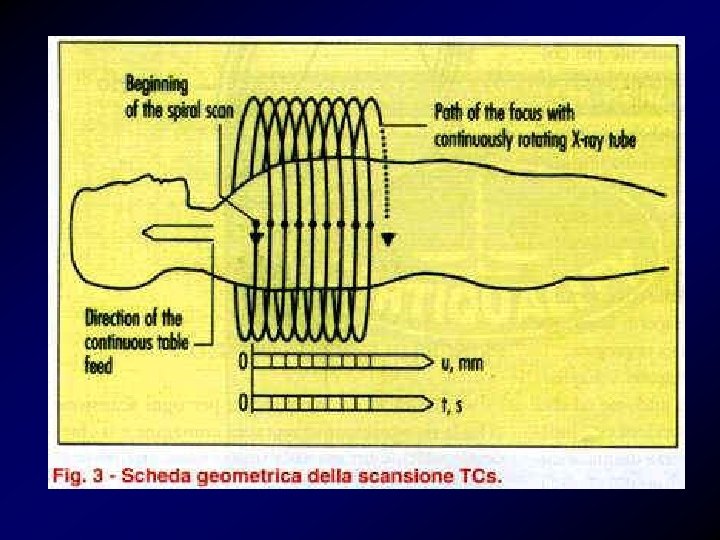

TAC spirale (angio-TAC) • La TC spirale del torace con m. d. c. permette di identificare embolie anche nelle arterie polmonari di IV ordine. E' una metodica di rapida esecuzione che si va sempre più diffondendo nella diagnostica della TEP.